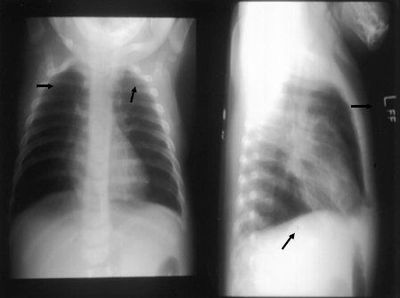

Question 17

Question

patología que se observa en la radiografía.

Answer

• enfisema

• atelectasia

• derrame pleural

• neumotorax

Question 18

• sx condensacion